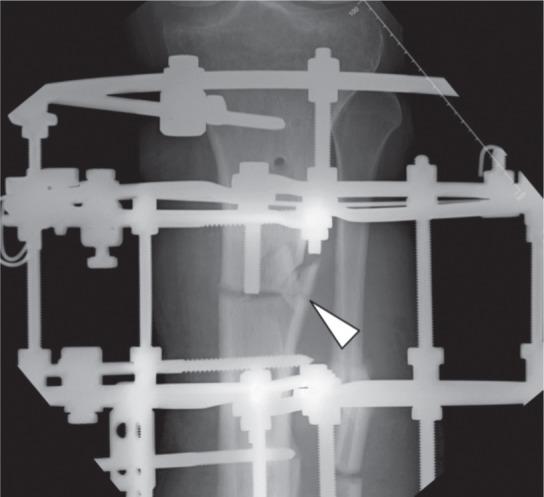

Corticotomy is an essential procedure for deformity correction and there are many techniques described. However there is no proper classification of the fracture pattern resulting from corticotomies to enable any studies to be conducted. We performed a retrospective study of corticotomy fracture patterns in 44 patients (34 tibias and 10 femurs) performed for various indications. We identified four distinct fracture patterns, Type I through IV classification based on the fracture propagation following percutaneous corticotomy. Type I transverse fracture, Type II transverse fracture with a winglet, Type III presence of butterfly fragment and Type IV fracture propagation to a fixation point. No significant correlation was noted between the fracture pattern and the underlying pathology or region of corticotomy.